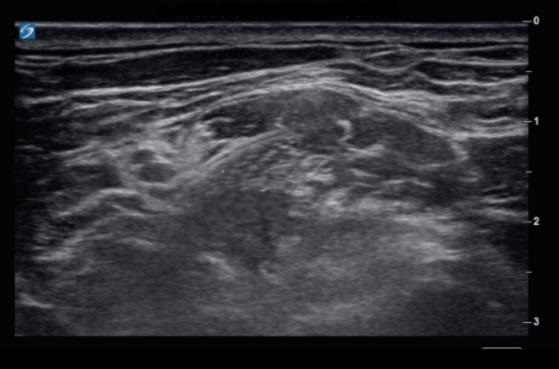

Interscalene Nerve Block - Continuous Catheter Image